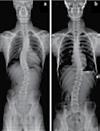

No. 1085 Thursday July 20, 2023 l ColoradoTimesNews.com 43 교통사고 후유증 / 목 통증 / 목 디스크 / 오십견 / 어깨통증 말초신경장애: 손, 발, 다리의 통증, 저림, 근육약화감, 감각상실 (편)두통 / 불면증 / 어지러움 / 턱관절 장애(TMJ) 척추측만증(Scoliosis) / 척추협착증 / 허리수술 후유증 허리통증 / 허리 디스크 / 관절염 / 좌골신경통 / 고관절, 발목, 손목 통증 ▪ ▪ ▪ ▪ ▪ ▪ ▪ ▪ ▪ 최첨단 목/허리 디스트 치료기기 최신형 디지털 X-ray 시설 Therapeutic Massage ▪초음파, 전기치료 Gonstead Chiropractic 교정치료 치료 진료과목 교통사고 치료 전문 자동차 보험 건강 보험 상해 보험 Southern California University of Health Science Doctor of Chiropractic 콜로라도주 척추신경 보드 정회원 캘리포니아주 척추신경과 보드 정회원 National Board 척추신경과 정회원 손석기 D.C. 원장, 척추신경 전문의 chiro1health@gmail.com Open Hours 월/수/금 9am-6pm 화/목: 2pm-6pm 청소년을 위한 척추교정 프로그램